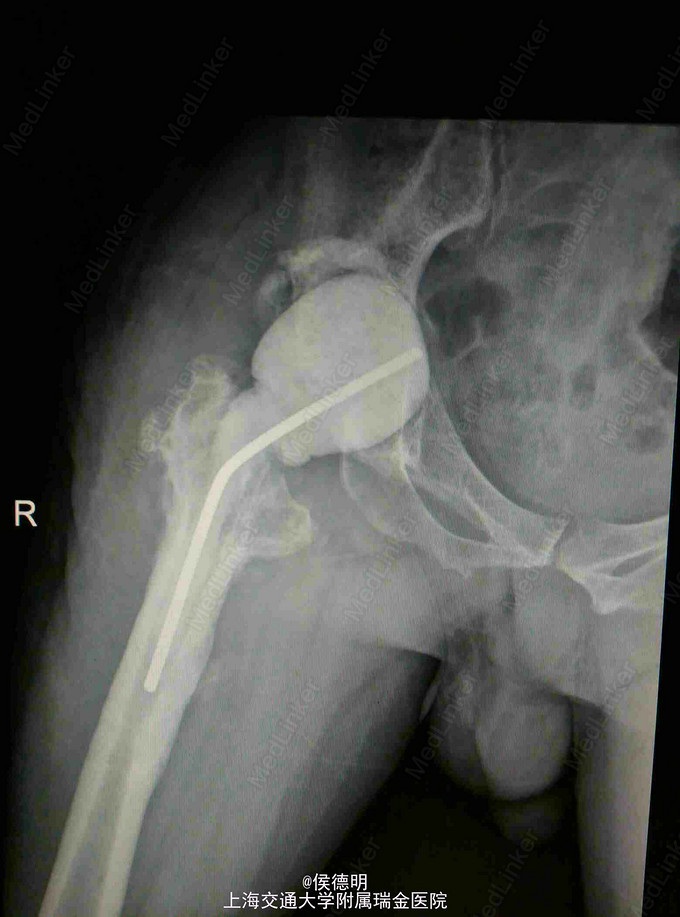

右侧髋关节疼痛1月余 患者3月前因“双侧股骨头坏死” 在外院行双侧THA术。术后3个月内右侧髋关节脱位3次。1月前患者出现右侧髋关节疼痛。休息不能缓解,不能走路。无肢体麻木,腰痛等症状。

查体: 右侧髋关节屈曲畸形。主动屈伸功能受限。皮肤切口为后外侧入路。皮肤无红肿。 辅助:MR提示假体周围大量积液。X片提示右侧髋关节脱位。三相同位素提示感染可能。

诊断:右侧髋关节脱位;髋关节假体周围感染可能。 治疗:右侧全髋关节一期翻修术(术中病理提示白细胞每高倍镜>10个)

随访:患者诉术后疼痛明显缓解。 讨论:术中发现髋臼完全松动。股骨柄明显放在了后倾的位置。因此术后频繁脱位。加强业务学习,避免低级失误。